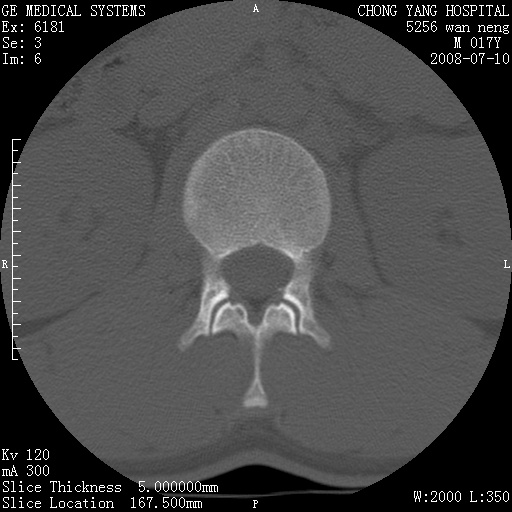

腰3、4椎弓崩裂

腰3、4椎弓不连

支持:腰3、4椎弓峡部崩裂。

腰3、4椎弓峡部不连

支持:腰3、4椎弓峡部崩解。

图片漂亮,目前也只能看到腰3、4骨质不连

腰3、4椎弓峡部裂。

腰3、4椎弓峡部裂。支持

支持腰3、4椎弓峡部崩裂。